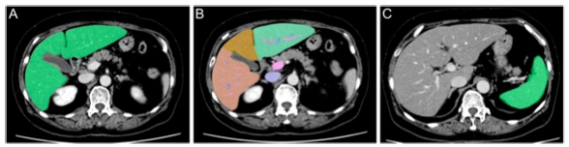

一位患有肝癌的67歲婦女的CT圖像。A TLV的軸圖像。原始數據被手動發送到工作站后,TLV實現自動測量。B 分割的TLV軸位圖像。鐮刀狀韌帶和中央肝靜脈被用作標志,分別從內側和外側分離出II、III和IV。C SV的軸位圖像。在這個工作站(ver5.5)中,SV是手動測量的

本項研究回顧性地分析了90名接受CTV和ECV的連續患者。手動放置感興趣區域的ECV(手動-ECV)、剛性登記ECV(剛性-ECV)和非剛性登記ECV(非剛性-ECV)的計算方法為:ECV(%)=(1-血紅蛋白)×(ΔHUliver/ΔHUaorta),其中ΔHU=平掃減去平衡(240s)。手動-ECV與CTV在估計LF方面進行了比較。測量了肝臟總體積與體表面積之比(TLV/BSA)、脾臟體積與BSA之比(SV/BSA)、TLV與SV之比(TLV/SV)、右肝體積與SV之比(RV/SV),以及肝段體積比(LSVR)。對ECV和CTV進行了ROC分析。

CT容積分析(CTV)和細胞外容積分數(ECV)是診斷LF的高度敏感和特異的工具。在CTV分析中,肝臟總體積(TLV)與體表面積(BSA)之比(TLV/BSA)、脾臟體積(SV)與BSA之比(SV/BSA)、TLV與SV之比(TLV/SV)、右肝與SV之比(RV/SV)以及Couinaud I-III段與IV-VIII段的體積比(肝段體積比:LSVR)都有助于評估LF等級。ECV是一個利用血細胞比容(Hct)、平掃CT和平衡CT計算的指數,對估計LF的程度具有重要的臨床價值。ECV需要通過放置感興趣區域(ROI)來測量CT值,這些區域由觀察者手動設置(手動-ECV)。ECV的剛性注冊(rigid- ECV)是指具有三維形狀的物體之間的對齊,并且只通過旋轉和平移進行。非剛性注冊ECV(nonrigid-ECV)是一種通過仿生變換使物體變形來對齊的方法。現階段,使用非剛性注冊的ECV在肝臟硬度測量方面已經引起了臨床上極大的關注。